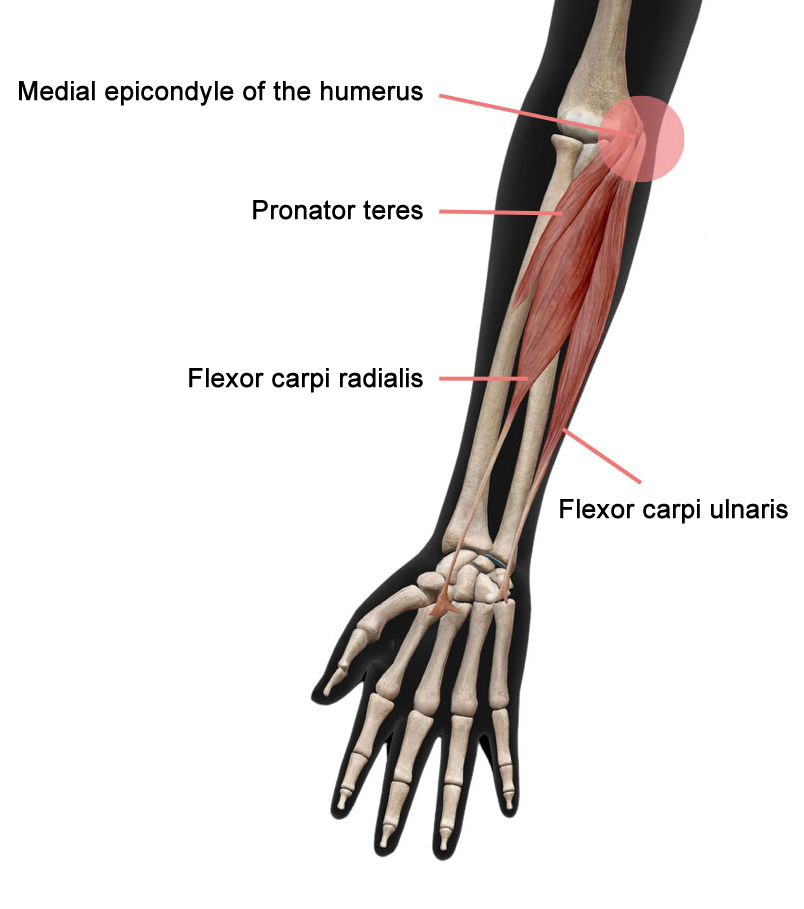

อาการปวดมีสาเหตุมาจากการบาดเจ็บหรือการอักเสบของเส้นเอ็นกล้ามเนื้อ ได้แก่

pronator teres, กล้ามเนื้องอข้อมือคือ flexor carpi radialis (FCR) และ flexor carpi ulnaris (FCU)

ซึ่งทั้งหมดมีจุดเกาะอยู่ที่ด้านในของข้อศอก คือ medial epicondyle of the humerus